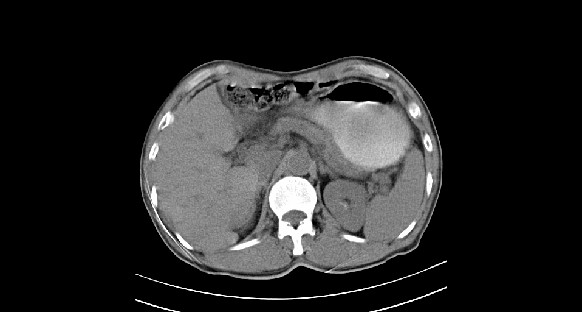

男性,70岁,体检b超发现左肾占位,请各位战友发表一下观点

左肾有两个病灶,且较大的病灶内可见点状钙化灶,增强扫描边缘也是呈渐进性强化,中央部分未见明显强化